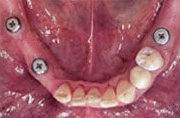

Früher wäre hier nur eine herausnehmbare Teilprothese infrage gekommen.

Fehlen mehrere Zähne, so spricht man vom teilbezahnten Kiefer. Solche größeren Zahnlücken konnten früher oftmals nur mit herausnehmbaren Teilprothesen geschlossen werden, wenn eine Brückenversorgung nicht mehr möglich war. Implantate erlauben, die Lücke mit einer implantatgetragenen festsitzenden Brücke zu schließen, ohne herausnehmbare Prothesen und ohne Abschleifen gesunder Nachbarzähne.